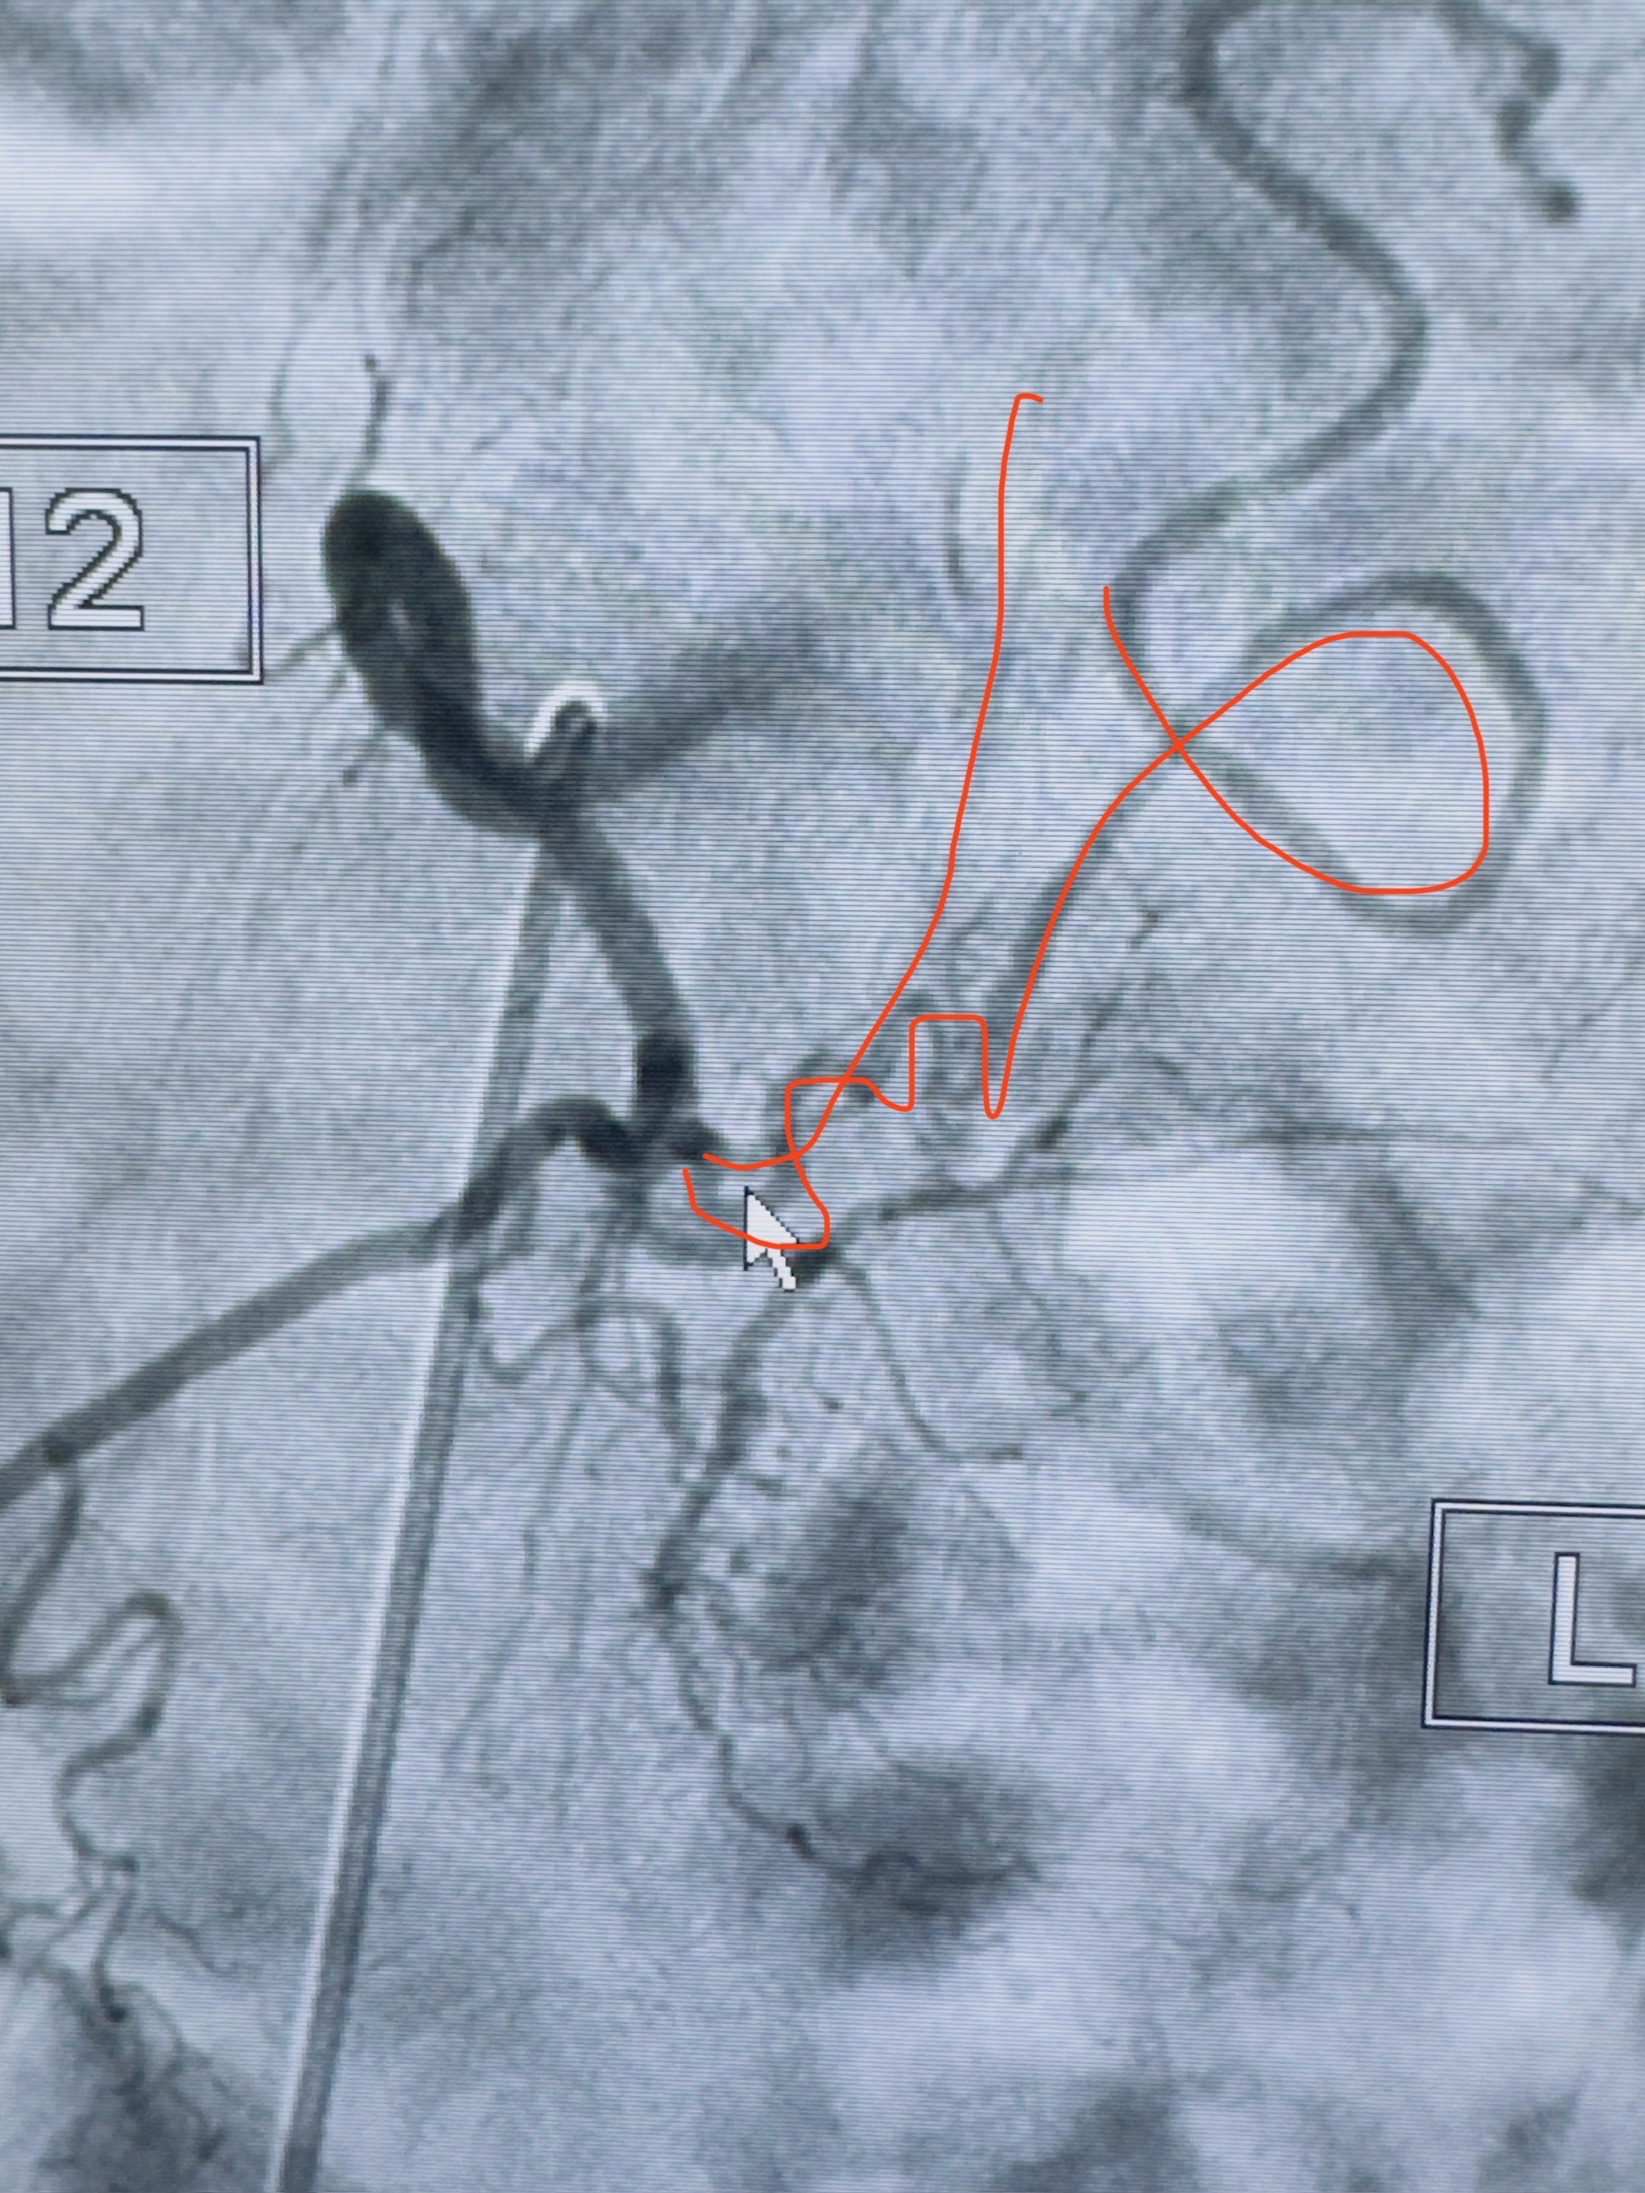

2023-10-13DSA:右侧L1水平硬脊膜动静脉瘘,供血动脉为右侧L1,附近动脉未见明确吻合供血,供血动脉处可见脊髓前动脉发出